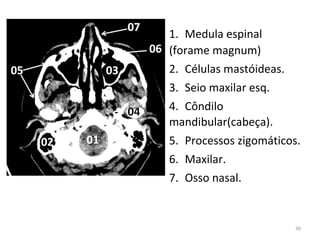

1. Medula espinal

(forame magnum)

2. Células mastóideas.

3. Seio maxilar esq.

4. Côndilo

mandibular(cabeça).

5. Processos zigomáticos.

6. Maxilar.

7. Osso nasal.